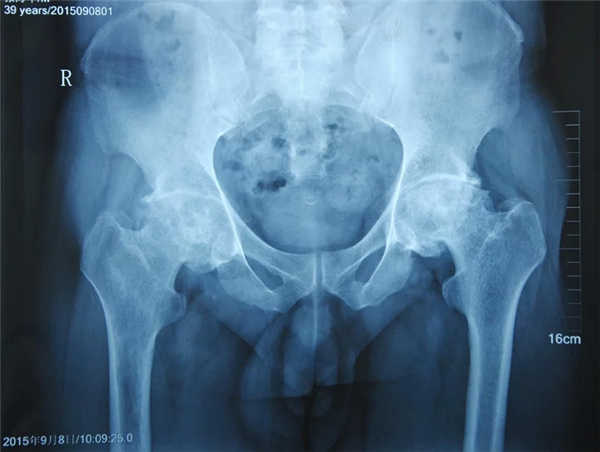

使用靶位体液渗透疗法治疗3个月:股骨头塌陷、骨缺损等问题得到一定缓解,病情好转

疼痛症状减轻,活动受限缓解